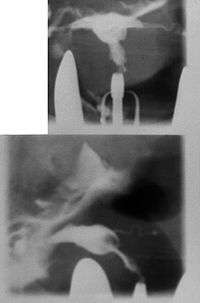

T-shaped uterus

A t-shaped uterus is a type of uterine malformation wherein the uterus is shaped resembling the letter t.[1] This is typically observed in DES-exposed women.[2] It is recognised in the ESHRE/ESGE classification,[3] and is associated with failed implantation, increased risk of ectopic pregnancy, miscarriage and preterm delivery. There is a surgical procedure to correct the malformation.[4]

Women are often diagnosed with this condition after several failed pregnancies, proceeded by exploratory diagnostic procedures, such as magnetic resonance, sonography, and particularly hysterosalpingography.[6][7][8] In such studies, a widening of the interstitial and isthmus of uterine tube is observed, as well as constrictions or narrowing of the uterus as a whole, especially the lower and lateral portions, hence the "t" denomination. The uterus might be simultaneously reduced in volume, and other abnormalities might be concomitantly present.[9]